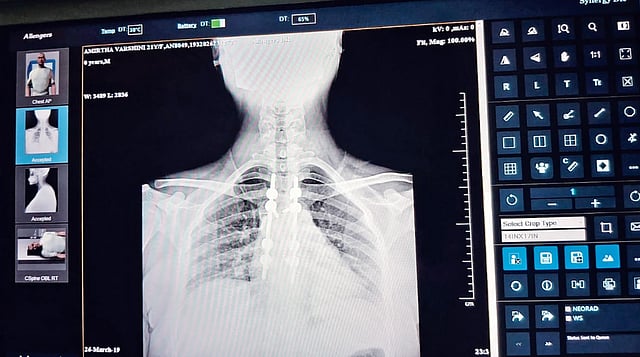

CHENNAI: A shortage of X-ray films has the Kilpauk Medical College (KMC) Hospital asking patients to take photos of x-ray images on their mobile phones and show them to doctors.

For a hospital that has a daily patient footfall in thousands, this raises serious concerns, as poor image quality could lead to misinterpretation and misdiagnosis, putting patient lives at risk.

Bharathi, who was visiting the hospital for his brother’s treatment for a broken wrist, asks how doctors can accurately diagnose conditions based on mobile phone images, as it could lead to incorrect treatment.

Dr S Perumal Pillai, president of the Government Doctors' Association, told this correspondent that x-ray sheet shortage is a statewide crisis, and most government hospitals are currently grappling with the problem. Perumal warned that if doctors are forced to diagnose patients by looking at images on their mobile phones, it could lead to misdiagnosis and put lives in danger. He noted that physical X-ray sheets remain the reliable way to accurately read and diagnose a patient's condition.

The Indian Council of Medical Research and the National Medical Commission provide specific frameworks for doctors using digital images for diagnosis. Under the Telemedicine Practice Guidelines, diagnosing a patient using a smartphone image of an X-ray is legally permissible, but it carries significant professional responsibilities and technical risks.